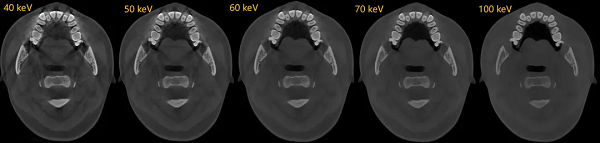

可靠的诊断始于清晰的影像。神农·云CT全新升级双能技术,能从物理层面有效识别并分离由金属植入物产生的伪影,显著降低其对周围关键解剖结构的干扰。

这项技术为种植规划提供了干净、可靠的影像基础,使医生能够清晰地辨识牙槽骨形态、骨小梁结构、神经管走向以及邻牙关系,将诊断依据从基础的“看得见”提升至精准的“看得准”,为后续每一步决策筑牢安全基石。

双能技术被称为传统成像的颠覆性技术,其不仅能实现对组织伪影的有效去除,更能特异性地对组织进行特殊处理,如去钙图/有效原子序数图等。

去钙图:双能技术可以有效识别骨质中的钙成分,并特异性地对钙成分进行抑制,而且这种抑制可以进行不同程度的调节;对于受骨钙成分影响较大的骨髓显影,有着优异的临床效果。